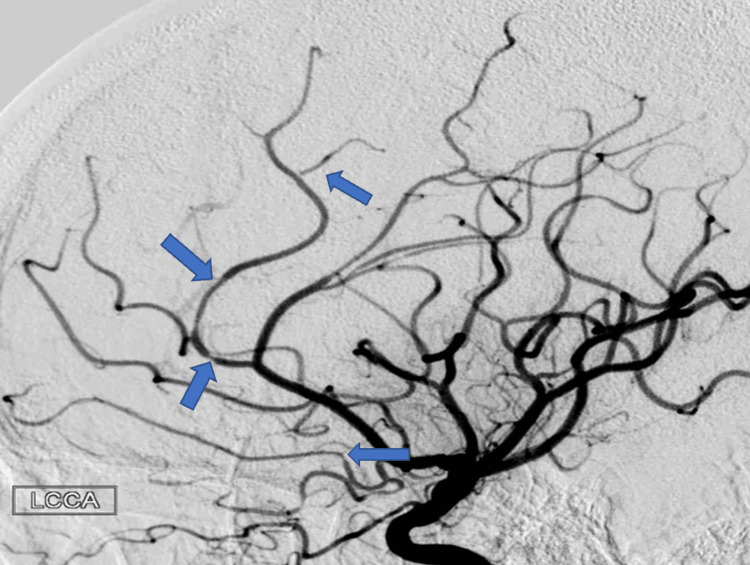

A year after her last outpatient appointment, she presented to the hospital with recurrent episodic thunderclap headaches with associated nausea, vomiting, and photosensitivity. Her neurologic examination was notable for aphasia without notable weakness. In the interim, she had established care with another neurologist who was closer to her home, who had discontinued verapamil and started the patient on venlafaxine for treatment of headaches and mood. CT Head without contrast revealed bilateral SAHs and a left frontal intraparenchymal hemorrhage, approximately 9.4 cc by ABC/2 formula (Figure 3). CTA Head and Neck with contrast again demonstrated multifocal stenosis of intracranial arteries. She underwent a second DSA, which demonstrated multifocal stenosis of intracranial arteries bilaterally (Figures 4–5). Angiogram found diffuse irregularities primarily affecting bilateral anterior cerebral arteries and, to a lesser extent, the bilateral middle cerebral and right superior cerebellar arteries. The patient also underwent brain biopsy with hematoma evacuation. Rheumatological workup was repeated and unremarkable. Lumbar puncture was performed and notable for mildly elevated glucose of 85 (normal range: 50-75 mg/dL) and mildly elevated protein at 46 (normal range: 15-45 mg/dL). Due to concern for PACNS as per discretion of treating physician at that time given the recurrence of symptoms and vascular irregularities, she was administered one dose of high-dose IV methylprednisolone, but this was discontinued when brain biopsy was planned. The biopsied temporal artery, dura, and brain showed no evidence of vasculitis. In the absence of any evidence for an ongoing inflammatory process, verapamil was restarted for symptomatic treatment of suspected recurrent RCVS. It was felt that RCVS was likely precipitated to exposure to SNRI. Venlafaxine was discontinued as this is a known precipitant of RCVS. After clinical improvement, the patient was discharged home and advised to continue verapamil, follow up with vascular neurology outpatient clinic, and undergo follow-up repeat vessel imaging.

Two weeks later, the patient underwent a repeat DSA, which showed interim improvement in multifocal stenosis with near resolution of the stenoses seen in the MCAs (Figures 7–8). During this study, a fistula between the right parietal middle meningeal artery (MMA) and the distal superior sagittal sinus was noted. Approximately four months later, the patient underwent onyx embolization of the MMA-sagittal sinus fistula. At the time of the writing of this article, the patient has not had any further recurrence of vessel irregularities, although she had been admitted for a brief hospital stays with complaint of headaches. Resolution of cerebral vessel irregularities has been confirmed on repeat DSA performed for arteriovenous fistula embolization.